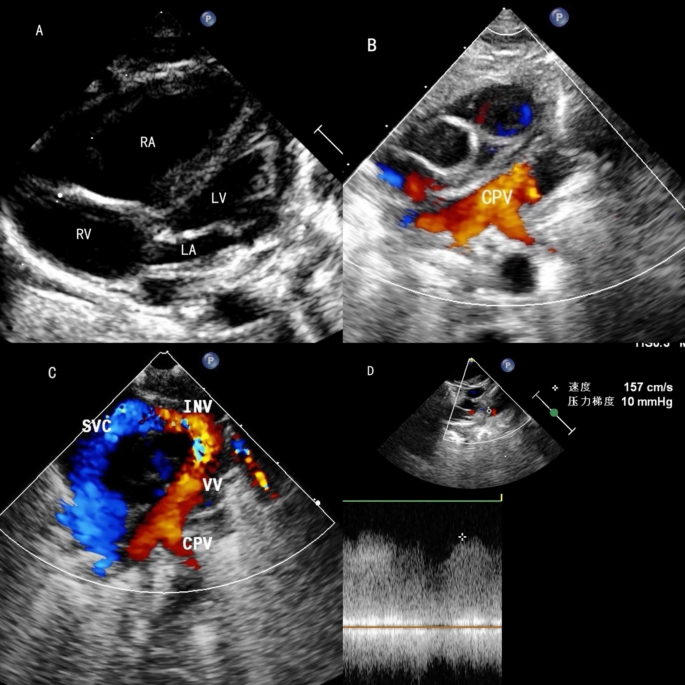

All 48 cases underwent echocardiographic examination to evaluate the pulmonary venous drainage pathways, the presence of obstruction, associated malformations, and cardiac function. Among the 15 supracardiac types, nine cases drained into the innominate vein and six into the superior vena cava (SVC) (Fig. 1). There were 13 single vertical vein and 2 cases of double vertical veins. In the 20 cardiac cases, 17 CPVs drained into the RA via the coronary sinus (CS) (Fig. 2), two CPV drained directly into the RA, and one had four pulmonary veins draining separately into the RA. Among the 10 infracardiac cases, eight cases had CPVs that drained into the portal vein via a vertical vein, one drained into the hepatic vein, and one drained into the inferior vena cava via ductus venous (Fig. 3). In the three cases mixed-type cases, all of them combines both supracardiac and cardiac types (Fig. 4).

The echocardiography of supracardiac TAPVC. (A) The left heart is extreme small. (B) The pulmonary veins drain into the CPV. (C) The CPV drains into the innominate vein via vertical vein. (D) An obstruction was detected at the drainage site.